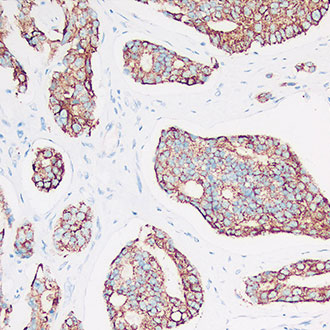

Cyclin D1

Cyclin D1 -